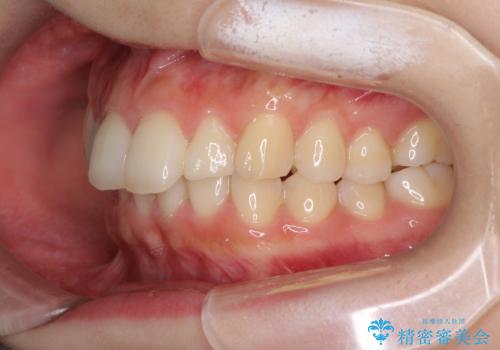

- 上の前歯が出っ張っている気がするとのことで来院された患者様です。

半年もせずにインビザラインを全く使用することができなくなってしまったので、治療開始から1年ほどでワイヤー矯正へ変更することとなりました。

ワイヤー矯正へ変更してからはあっという間に治療が進み、1年弱で終えることができました。